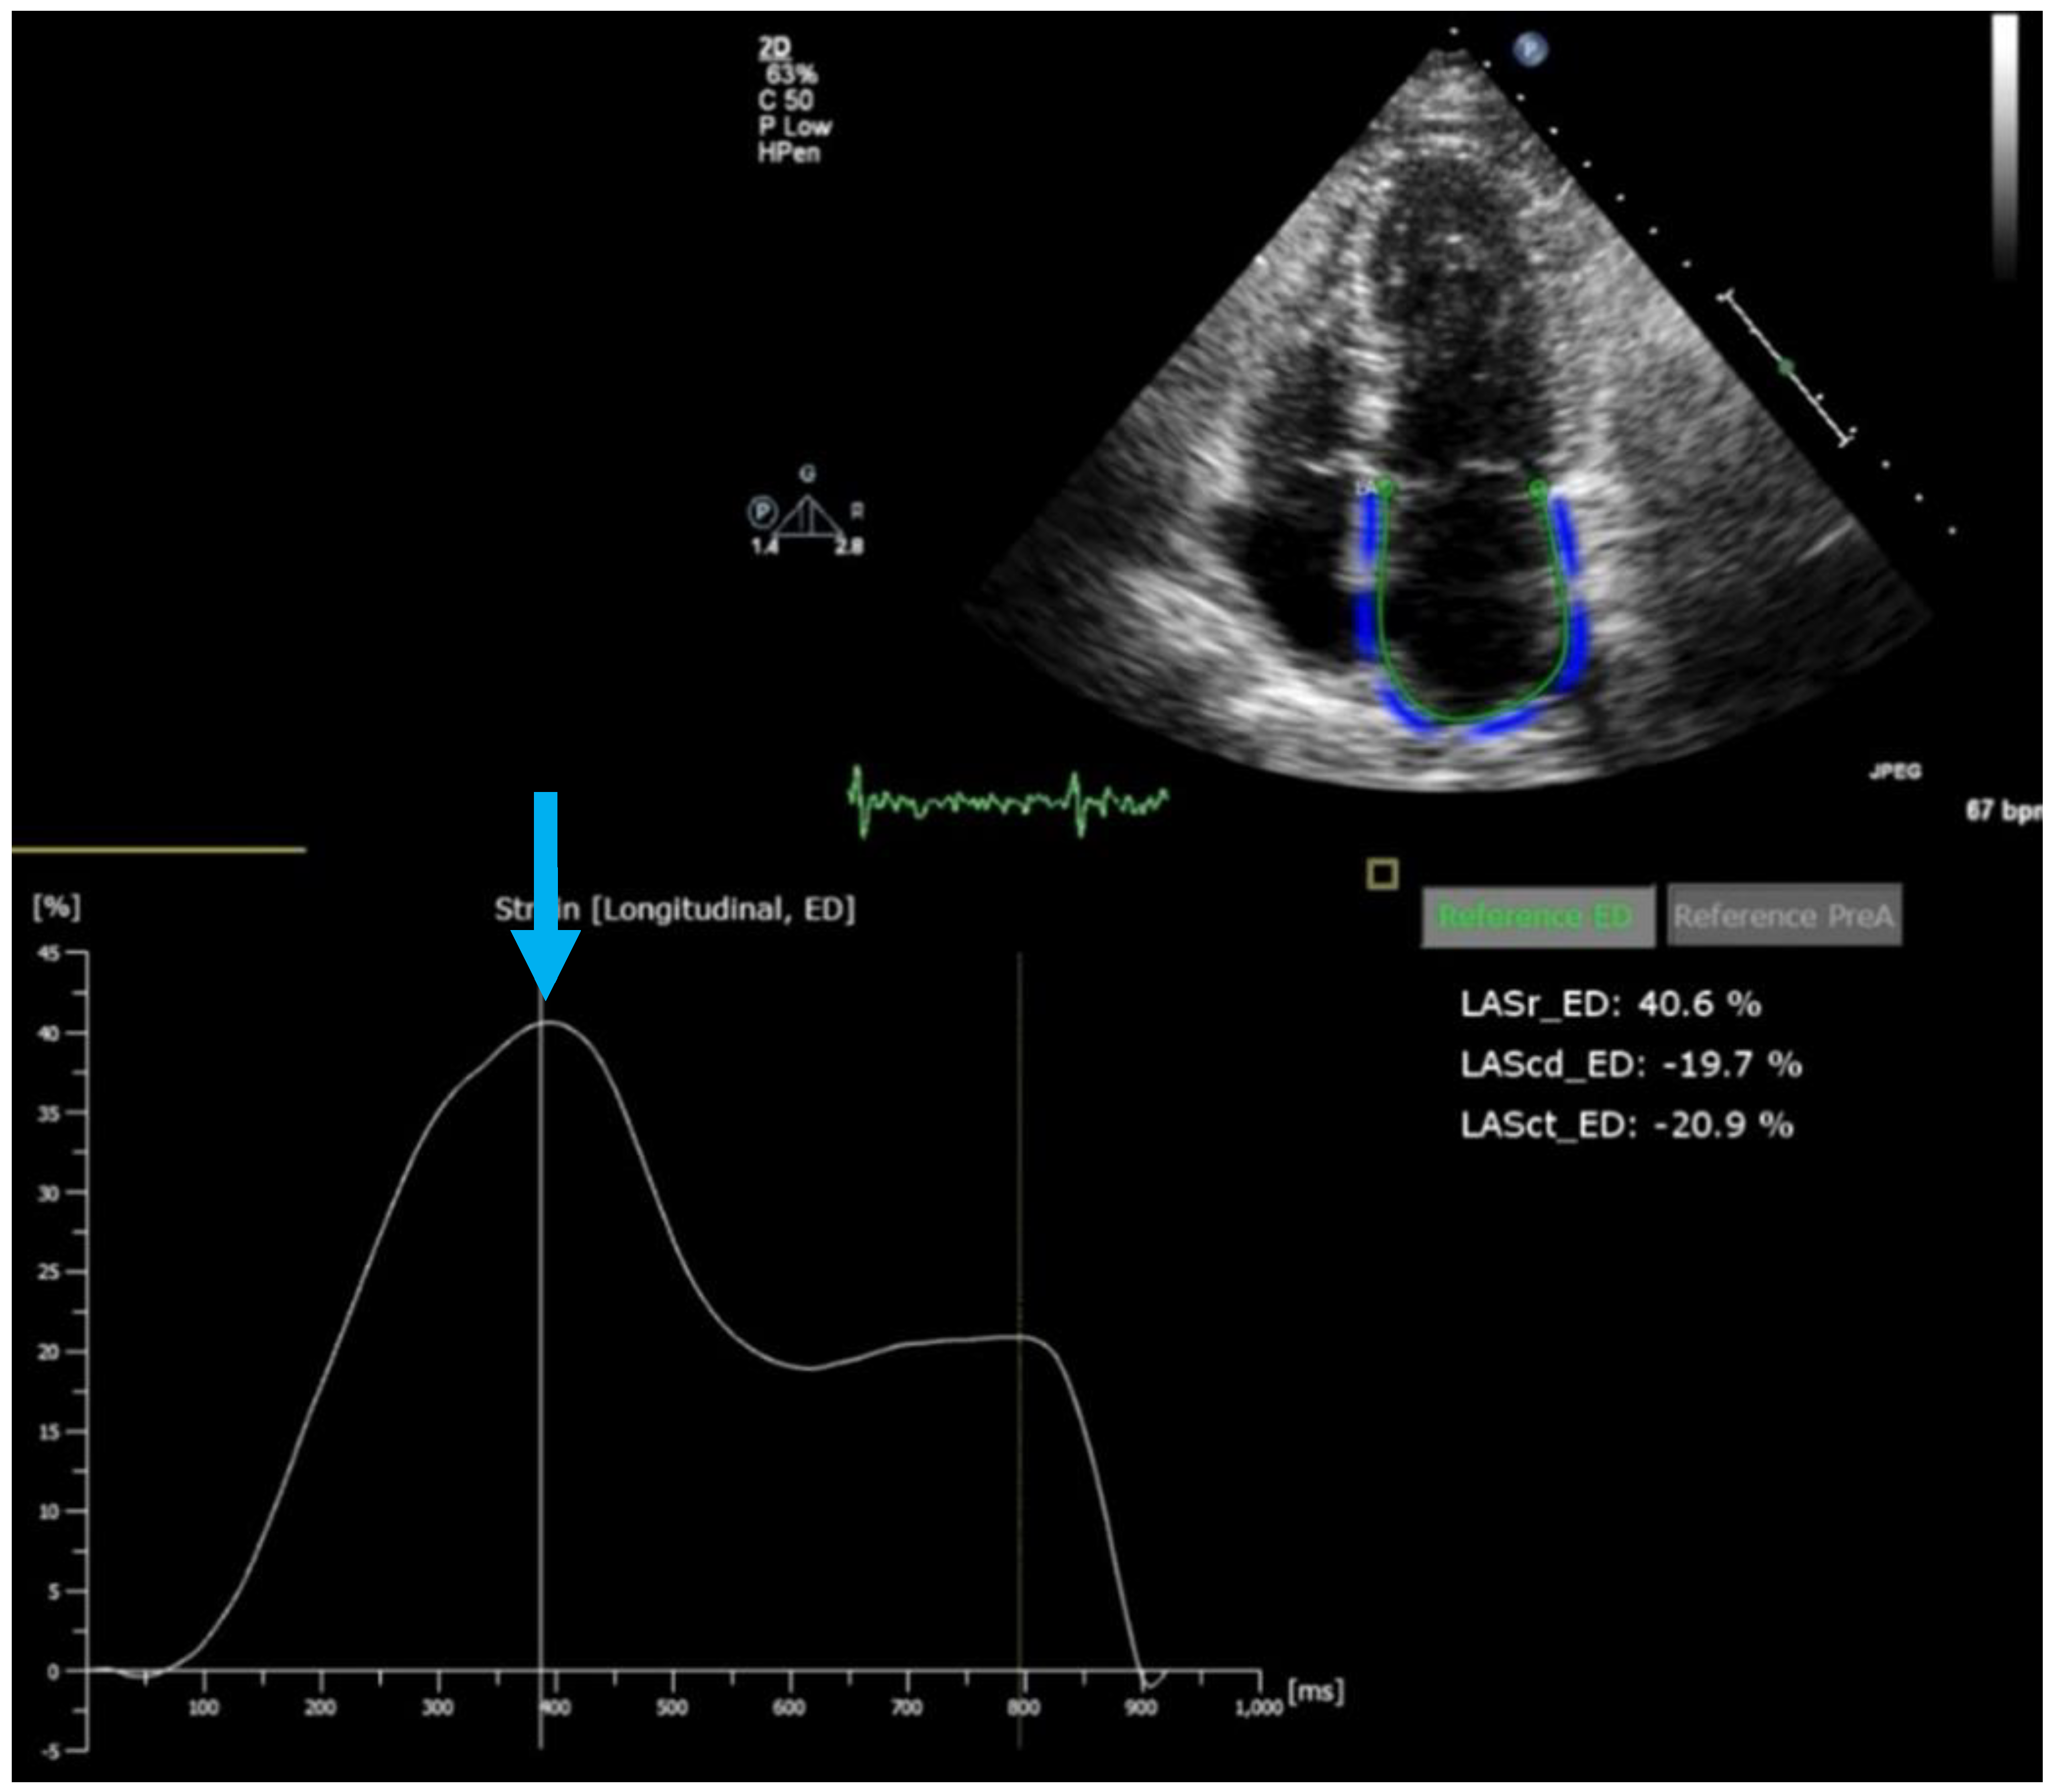

- Pixel-wise maps of the magnetic relaxation parameters T1, T2, and T2*, called “parametric imaging”, allow a limited characterization of underlying tissue ([37]; Figure 5). Additionally, by pre- and post-contrast registration of T1 in the myocardium and blood pool, a direct relative measure of extracellular volume (in percent) for each pixel can be calculated. For example, hemochromatosis leads to shortening and amyloidosis leads to lengthening of T1 relaxation times, which sets these pathologies apart from others. Myocardial edema leads to lengthening of T1 and T2 times and the expansion of extracellular volume, which in themselves are non-specific, but may aid in the diagnosis of, e.g., myocarditis, depending on clinical circumstances. Notably, increased extracellular space may be indicative of diffuse fibrosis but also, e.g., tissue edema. Hence, although, for example, an increased T1 value does correlate modestly with myocardial fibrosis and may, therefore, support the diagnosis of diastolic dysfunction and HFpEF, the relaxation parameters are multifactorial and should not be mistaken for true histology.